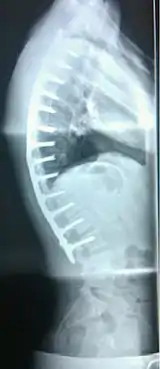

Scheuermann's disease is considered to be a form of juvenile osteochondrosis of the spine. It is found mostly in teenagers and presents a significantly worse deformity than postural kyphosis. Patients suffering with Scheuermann’s kyphosis cannot consciously correct their posture. The apex of their curve, located in the thoracic vertebrae, is quite rigid.

In addition to the pain associated with Scheuermann's disease, many sufferers of the disorder have loss of vertebral height, and depending on where the apex of the curve is, may have a visual 'hunchback' or 'roundback'. It has been reported that curves in the lower thoracic region cause more pain, whereas curves in the upper region present a more visual deformity. Nevertheless, it is typically pain or cosmetic reasons that prompt sufferers to seek help for their condition. In studies, kyphosis is better characterized for the thoracic spine than for the lumbar spine.[6][7]

The seventh and tenth thoracic vertebrae are most commonly affected. It causes backache and spinal curvature. In very serious cases it may cause internal problems and spinal cord damage, but these cases are extremely rare. The curvature of the back decreases height, thus putting pressure on internal organs, wearing them out more quickly than the natural aging process; surgical procedures are almost always recommended in this case.